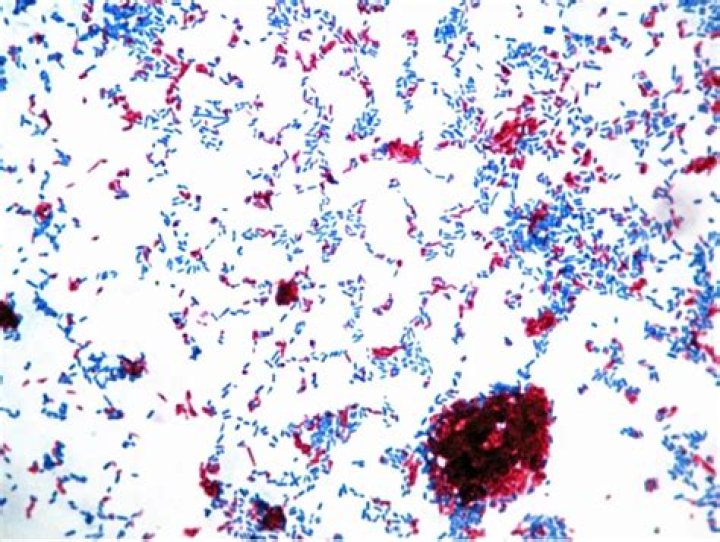

What is the most common stain used to diagnose Mycobacterium species?

Acid-Fast Bacteria—Ziehl– Neelsen Stain

This stain is used to identify Mycobacterium tuberculosis, the causative agent of tuberculosis. Acid-fast organisms have a lipoid capsule that has a high molecular weight and is waxy at room temperature.

Is Staphylococcus epidermidis acid fast stain?

The darker staining cocci are Staphylococcus epidermidis , a non-acid fast bacterium.

How does acid fast stain work?

The cells in the sample hold onto the dye. The slide is then washed with an acid solution and a different stain is applied. Bacteria that hold onto the first dye are considered "acid-fast" because they resist the acid wash. These types of bacteria are associated with TB and other infections.